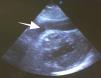

Después de 36h de la intervención la paciente presenta diaforesis; se realiza radiografía de tórax sugiriendo que el electrodo ventricular del cardiodesfibrilador implantable (CDI) se encontraba fuera del corazón (figs. 1 y 2); minutos después la paciente presenta palidez, frialdad generalizada con taquicardia e hipotensión severa; al examen físico se obtiene TA: 64/30mmHg; FC: 120lpm; FR: 30rpm, SatO2: 91%, ruidos cardiacos velados y ecocardiograma el cual muestra colapso ventricular derecho, derrame pericárdico y el electrodo (figs. 3 y 4), por lo que es trasladada inmediatamente a salas de cirugía con la sospecha de taponamiento cardiaco; se realiza esternotomía media evidenciando: hemopericardio aproximadamente 2.000cc, soluciones de continuidad en número de 2 en el ventrículo derecho, la primera puntiforme de 4mm, correspondiendo al electrodo de fijación auricular el cual se movilizó muy probablemente durante el preoperatorio, dado que en la radiografía prequirúrgica se encontraba normoinserto, y otra de 3cm en la pared anterior del ventrículo derecho a través de las cuales emergen los electrodos de fijación activa del dispositivo (fig. 5), con sangrado activo masivo, aurículas, ventrículos y grandes vasos colapsados; se introduce sonda Foley sobre defecto de mayor tamaño con posterior insuflación de la misma controlando parcialmente el sangrado, cardiorrafia y paso de hemoderivados directo al corazón por la sonda; presenta asistolia requiriendo maniobras de reanimación cardiocerebropulmonar avanzadas durante 20min sin obtener respuesta, por lo que la paciente fallece.

El diagnóstico de la perforación ventricular secundaria a electrodos de marcapasos la podemos identificar y confirmar con radiografía de tórax como lo observamos en nuestro caso, en el cual se encontraba el electrodo ventricular fuera de la cámara cardiaca. Otros métodos diagnósticos pueden ser el fluoroscopio, la ecocardiografía o TAC de tórax, encontrándose en esta última alteraciones de hasta el 15% de pacientes asintomáticos durante los controles postimplante del dispositivo10,23,24. En el ecocardiograma tridimensional podemos obtener una mayor precisión que en la TAC de tórax en la identificación de la perforación ventricular por electrodos, debido principalmente al efecto tomográfico conocido como «estrella» causado por los materiales del electrodo (figs. 8 y 9), haciendo difícil el diagnóstico. No existe consenso sobre criterios radiográficos diagnósticos universalmente aceptados entre los grupos de radiólogos, por esto la correlación clínica nos orienta. Todos estos estudios orientan al diagnóstico, pero la no evidencia del electrodo fuera del corazón no nos descarta la complicación, como sucedió en nuestro caso donde hubo una migración del electrodo de fijación activa auricular derecho con posterior perforación del ventrículo ipsilateral, lo cual nos muestra una complicación aún más infrecuente debido a la perforación ventricular por el electrodo ubicado en la aurícula17,25,26.